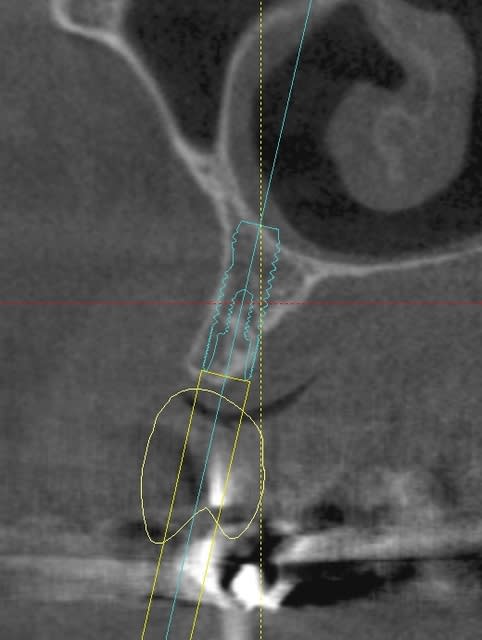

une petite étude de ton cas avec implants osseosped Astra :

12 : 3.5 x 11

13 : 3 x 11 (?)

14 : 3 x 11 (?)

15 : 3.5 x 11 (?)

16 : 4 x 11

17 : 4 x 11

je ne pratique pas donc pas de conseils sur ces implants.

techniquement:

extraction de 12 , curetage soigneux.

vue la qualité osseuse :

si D4 :

saignée à la lame n°15

si D3 :

avec un disque diamanté 10 x 0.3mm incision crestale de 12 à 16 ou 17

puis avec un disque de 20x0.3mm ou à la lame 15 approfondissement de la saignée

puis expansion en "douceur" (sans incision de décharge verticale, à priori car la ligne de crête est relativement droite)

pose de tes implants et dans ce cas, le VitalOs me semble idéal.

la difficulté majeure sera la corticale palatine qui ne semble pas géniale et qui méritera une attention particulière, ostéotome de Tatum +++

honnêtement je ne commencerais pas par un cas comme celui ci sans une solide connaissance de la sensibilité osseuse.

pas de provisoire